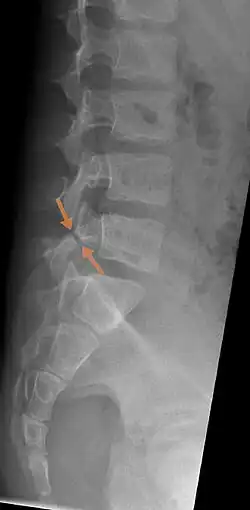

| Arrows show break in pars interarticularis at L5. X-Ray of lumbar spine, lateral projection, in an 11-year-old boy | |

The scottie dog sign It was once used as a diagnostic sign in x-rays, for lumbar spondylolysis, but it is not commonly in use nowadays because of the advent of more sensitive diagnostic methods such as the CT scan and MRI scan. If spondylolysis is present, the pars interarticularis, or the neck of the dog, gives the appearance of a Scottish Terrier with a collar around its neck.[7]

X-Ray

X-rays (electromagnetic radiation) are projected through the body to produce an image of its internal structures. The radiation is more attenuated (absorbed) by the denser tissues of the body (i.e. bone) than the softer tissues (i.e. muscles, organs, etc.) creating a picture composed of shades of grey ranging from white to black. A vertebra with a fracture or defect of the pars interarticularis will have a dark mark through this region of bone. Since this is difficult to see on the AP (anterior posterior) x-ray view an oblique x-ray of the lumbar spine can usually identify the spondylolysis. If inconclusive a further CT scan can produce a 3-dimensional images to more clearly show the defect although the exam increases the patients radiation dose by at least an order of magnitude than plain x-rays.[16][17]